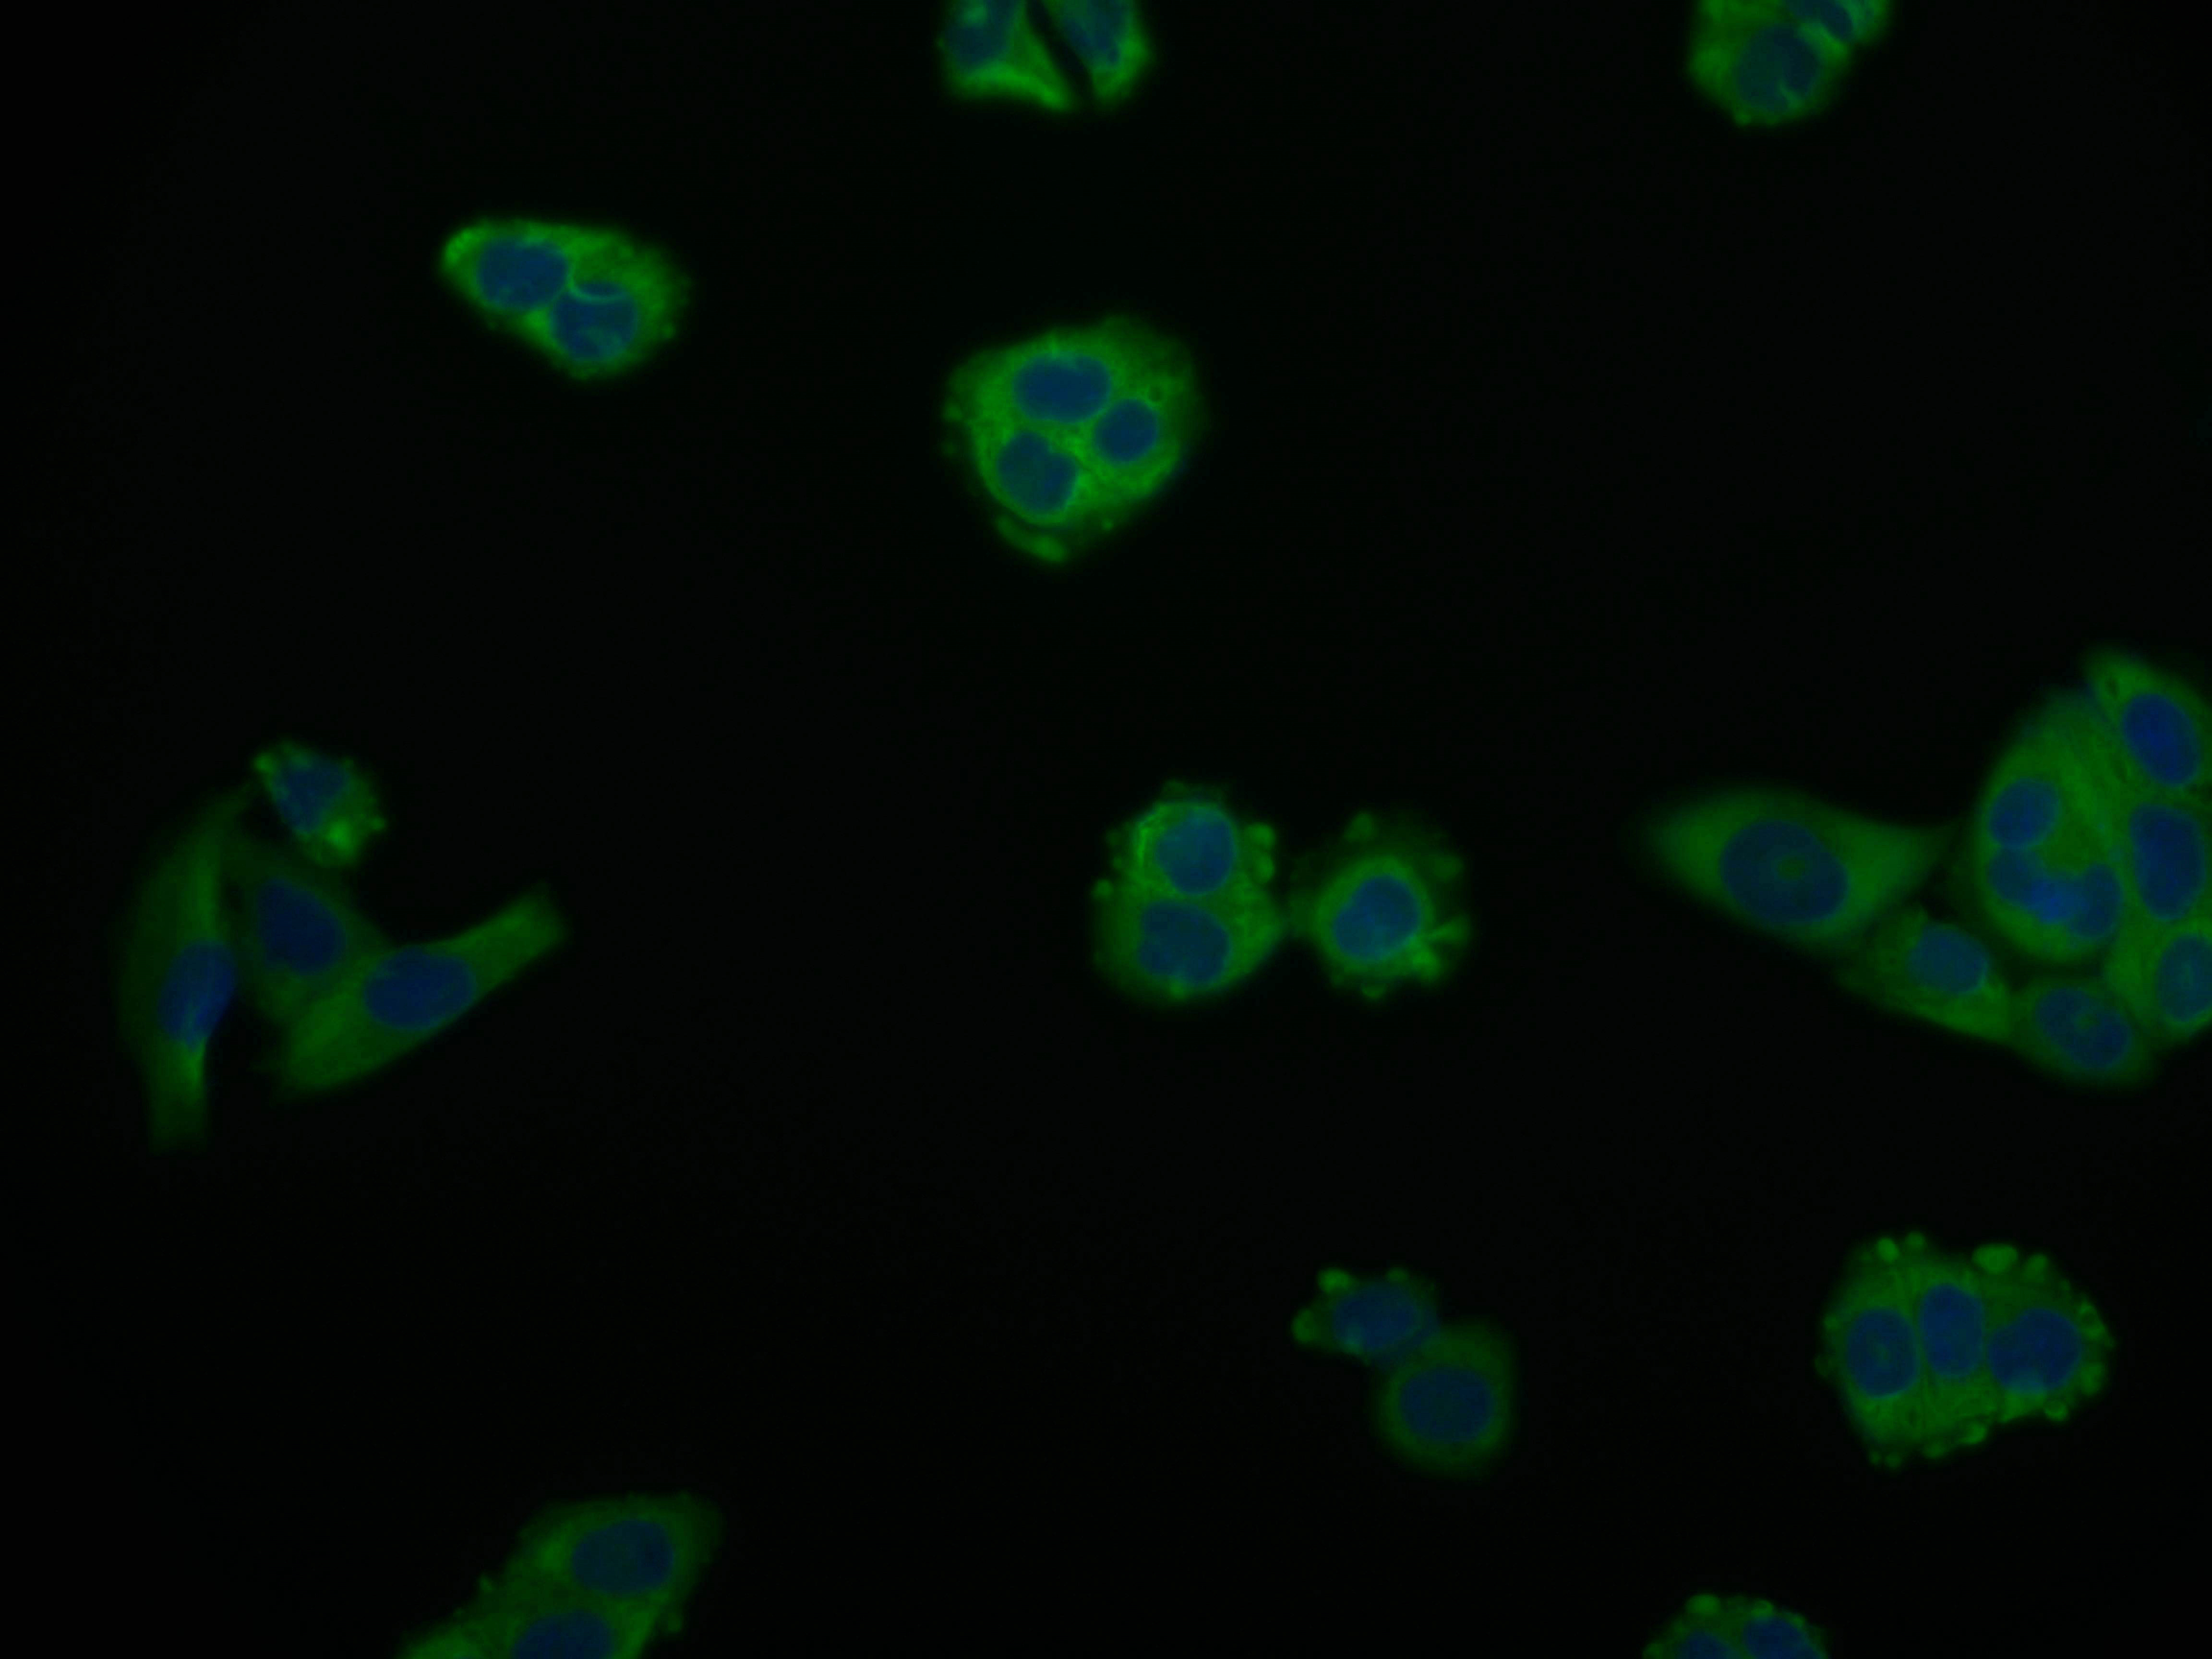

Immunofluorescence staining of PC-3 cell with CSB-RA216908A0HU at 1:50, counter-stained with DAPI. The cells were fixed in 4% formaldehyde and blocked in 10% normal Goat Serum. The cells were then incubated with the antibody overnight at 4°C. The secondary antibody was Alexa Fluor 559-congugated AffiniPure Goat Anti-Rabbit IgG(H+L).